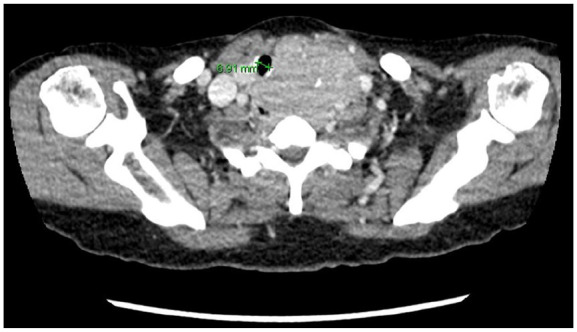

Preoperatively, the thyromental distance was greater than three finger breadths,6 the Mallampati score was 2,7 and there was no head and neck motion limitation.6 Furthermore, it was confirmed that the airway was intact up to the glottis level. However, chest radiography and neck computed tomography showed marked narrowing of the trachea, along with deviation to the right (Figures 1 and 2). It was apparent that careful anesthetic planning was crucial to minimize unexpected difficulties during intubation.

Figure 2.

Neck CT showing tracheal narrowing.